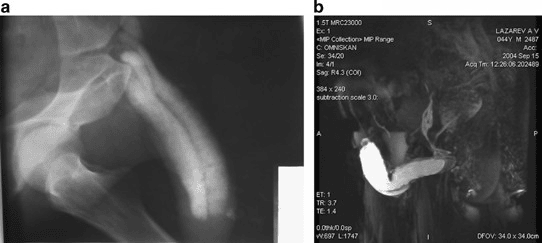

Erectile dysfunction - diagnostics:

A 43-year-old patient: (a) pharmacocavernoso-graphy does not show venous leakage clearly. (b) MRI: significant venous leakage (mixed type) is visualized including caverno-balanic shunt. ANOVA IRM - Germany

Based on our specific diagnostics using ultrasound imaging of the penis and penile arteries (doppler and duplex US) as well as magnetic resonance imaging (MRI) and angiography (MRA) of the arteries supplying the penis, we can, in contrast to many other clinics, deliver the stem cells with image support, e.g. using CT, precisely to the affected area. This means we can inject into and at the site of damage or cause to specifically and quickly trigger an effect where needed. All interventions are performed under supervision and care of our anesthesiologist and are pain free.